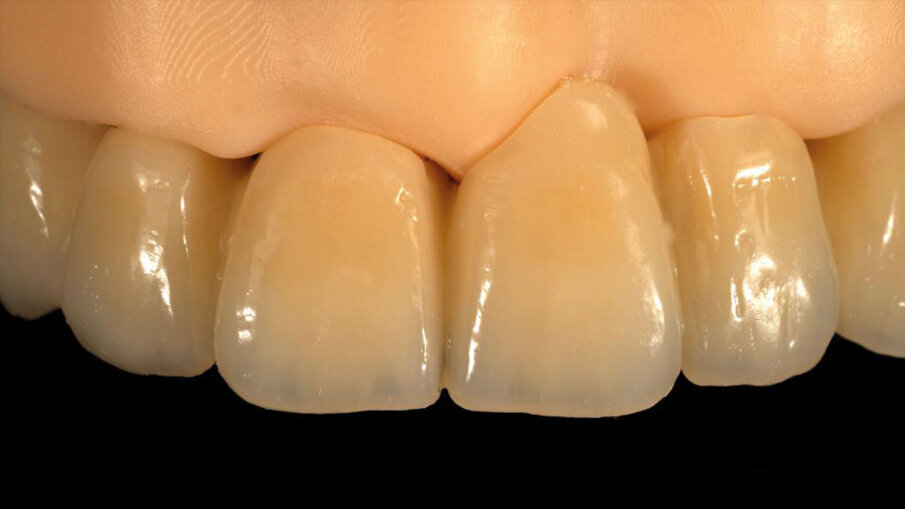

Per la realizzazione del provvisorio, si è collaborato con l’odt. Nicola Palladino del laboratorio Dent-One di Imola (BO). Grazie ai flussi digitali, è stato possibile collaborare a distanza fin dalle fasi iniziali, a partire dalla progettazione della ceratura diagnostica che ha guidato l’intera pianificazione implantare, mantenendo il concetto di “implantologia protesicamente guidata”.

Lo scambio di informazioni tramite file STL ha permesso di trasferire al laboratorio preziose informazioni sulle emergenze dei componenti protesici scelti e sulla loro relazione con i tessuti prima dell’intervento. Sulla base di queste informazioni, il laboratorio ha potuto costruire un provvisorio da cementare sulle torrette alla fine dell’intervento, simulando virtualmente il profilo dei tessuti molli dopo le estrazioni (Figg. 17-19).